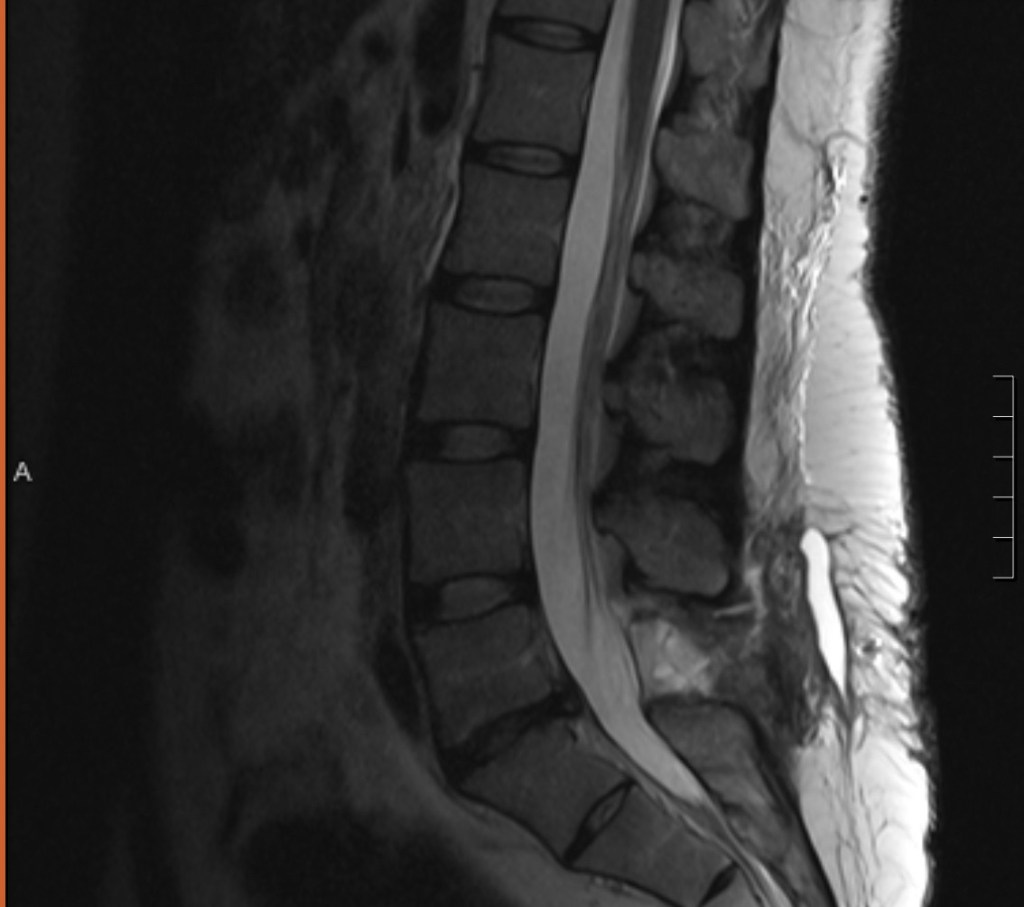

My last post was October 1st. So much has happened since then. A surgeon told me yesterday, “You have Cauda Equina Syndrome. Not only did you have a serious spinal surgery, you had a serious EMERGENCY spinal surgery. It’s serious and is going to take a long time for your body to recover.”

I was starving. In pain. Miserable. I can’t tolerate narcotics so I opted for Tylenol and Toradol. They were short on IV fluid from the Hurricane Milton and refused to let me eat should I need urgent surgery. The wait was miserable. After about 7 hours, I was brought back to get an MRI.

I thought this MRI would be less painful than the one I received directly prior to emergency surgery, but boy was I wrong. The pain was excruciating. I clenched my teeth and tried to stay as still as possible. Somehow, I made it through. Tears stung in my eyes as I rolled my body over to transfer to the hospital cot. Although it was originally very embarrassing, I was getting used to being transported across the hospital in a bed.

The radiologists looked at me and said, “We are so sorry. That looks very painful.” The way they said it made me nervous. Immediately upon arriving back at my designated hallway spot, the nurse came over and said, “Anything you need for pain, I can get you.” I told her that I needed pain meds since my back was now on fire from the MRI. Another nurse came over to take blood. I looked up the order on My Chart and realized that the test was a pre-operative screen. Did they think I needed surgery?

After reading and googling, I was certain that my surgeon tore my dural sac and that I had cerebrospinal fluid was leaking into my back. The attending doctor came to talk to me and mentioned that maybe they would drain the fluid. She seemed just as concerned as me.

Another hour later, he returned. He told me that the team was concerned about urgent surgery and that although the MRI interpretation mentioned impingement of the descending right nerve roots, I did not have Cauda Equina Syndrome again. I was going to be able to go home. I was given information for follow-ups with the spine team, given some new prescriptions for nerve pain, and discharged.

I made it back to my bed. The spine team came by shortly thereafter and told me that the preliminary results of my MRI were could and that they didn’t see a herniation or nerve impingement. They told me “Recovery from Cauda Equina isn’t linear.” That there would be good days and tough days but that it was a bumpy road and a serious condition that took a long time to resolve. They said due to the extent of my pain they wanted to do a CT scan and an X-ray to rule out anything further. I went and got these tests done and was brought back to my bed.

After she left I typed a-r-a-c-h-n-o-i-d-i-t-i-s into Google. It read, “Arachnoiditis is a rare pain disorder caused by inflammation of the arachnoid, one of the membranes that surrounds your spinal cord. It can cause severe pain and neurological symptoms, such as muscle weakness. Symptoms may become more severe or even permanent if the condition progresses. Many people with arachnoiditis are unable to work and have a significant disability because of pain. Unfortunately there is no cure for arachnoiditis. It may be progressive.” It was caused by spinal fluid leaking and making your nerves “sticky” and clumped together. This made sense given my last MRI.

He seemed to start backtracking so I asked him flat out if I had it. He said that I should defer to the spinal team. The ones that told me my MRI LOOKED OKAY. To make a long story short, the radiology resident typed up a finding of Arachnoiditis, the attending ER doctor read it and called the Neurology team to report out. Meanwhile, the attending radiologist amended the report after not seeing Arachnoiditis (thank you God, that is the power of prayer 🙏🏻). Overall, my MRI looked better and showed no herniation.